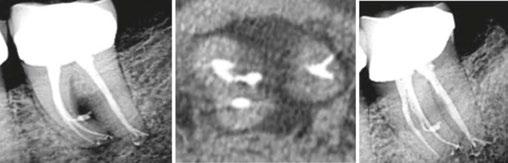

Additionally, with IRR, the outline of the root canal is usually distorted and appears contiguous with the resorptive defect, while with external resorption, the root canal outline appears normal and can usually be seen running through the radiolucent resorptive defect, as there remains a thin layer of dentin separating the canal from the resorptive area9-10 (Figures 2A-2D).

Figures 2A-2D: 2A: Periapical radiograph of tooth No. 21. Large resorptive defect is noted in external cervical region. Blue arrows point to a thin layer of predentin that appears to be running through defect. Outline is what remains of root canal wall. Tooth tested vital, and diagnosis of invasive cervical root resorption was made. Due to minimal remaining tooth structure, extraction was advised. 2B-2D: Sagittal, coronal, axial slices show resorptive defect external to root canal

Figures 3A-3H: 3A. Preoperative periapical radiograph of tooth No.10 showing internal root resorption in apical third of root. There is significant alveolar bone loss adjacent to defect. 3B. Sagittal CBCT image of tooth No. 10 showing internal resorptive defect perforating on mesial aspect of root. Note adjacent alveolar bone loss extending proximally to tooth No. 9. 3C. Axial CBCT image of internal resorptive defect perforating on mesial aspect of root. There is thin layer of circumferential dentin remaining and extensive alveolar bone loss adjacent to the defect. 3D. Periapical radiograph showing gutta-percha cone fit. Gutta-percha cone passes through resorptive defect to contact apical portion of root canal. 2E. Immediate postoperative periapical radiograph of tooth No.10 once root canal was completed and resorptive defect was restored. 2F. Two-year follow-up showing complete healing of radiolucency adjacent to defect and reestablishment of PDL. 2G. Two-year follow-up CBCT. Coronal slice showing complete healing of radiolucency adjacent to defect and reestablishment of PDL. 2H. Five-year follow-up radiograph. Patient is completely asymptomatic